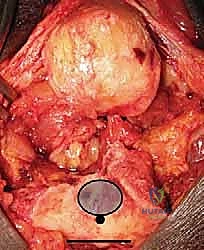

3. إزالة العظام المحطمة وتحضير القناة العظمية

بمجرد الوصول إلى المفصل، يتم تقييم حجم الدمار. تُزال الشظايا العظمية المفتتة التي لا يمكن إنقاذها. بعد ذلك، يتم تحضير القناة الداخلية لعظم العضد (من الأعلى) وعظم الزند (من الأسفل) باستخدام أدوات قياس دقيقة جداً لضمان تطابق المفصل الصناعي مع تشريح المريض.